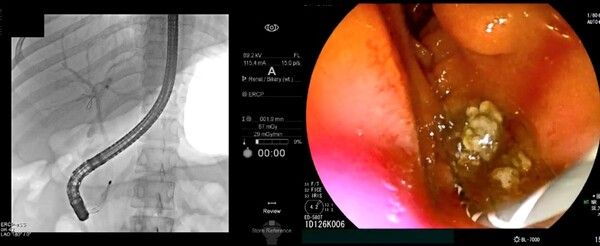

ERCP 시술을 통해 담관결석을 제거하는 모습. 한림대의료원 제공 [뉴스락]

초음파내시경으로 담관결석이 관찰되면 내시경적 역행성 담췌관조영술(이하 ERCP)을 통해 담관결석을 제거한다.

ERCP는 특수내시경과 방사선을 이용한 시술로, 내시경을 십이지장까지 삽입하고 십이지장 유두부를 통해 담관에 관을 넣고 조영제를 주입해 담석의 정확한 위치를 확인한다.

이후 미리 넣어놓은 가이드선을 따라 바스켓 또는 풍선 기구를 담관으로 넣어 담석을 제거한다. ERCP로 담관결석을 제거한 뒤에도 재발을 막기 위해 담낭담석을 제거하는 담낭절제술이 필요하다.

ERCP는 개복 등 수술적 치료 없이 내시경시술을 통해 담관결석을 제거할 수 있지만 시술 난이도가 높고 침습적 치료이기 때문에 드물게 부작용과 합병증이 발생할 수 있다. 특히 십이지장 유두부가 매우 좁아 결석을 빼내기 위해 유두부 괄약근을 절개하는 과정에서 출혈이나 천공 등의 위험이 있다.